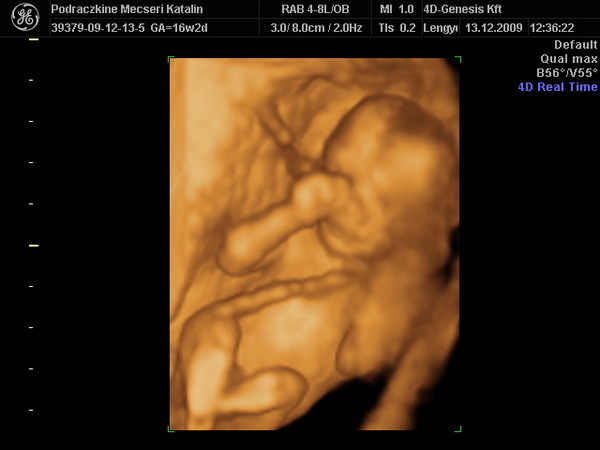

Kép Itt puszit kűld